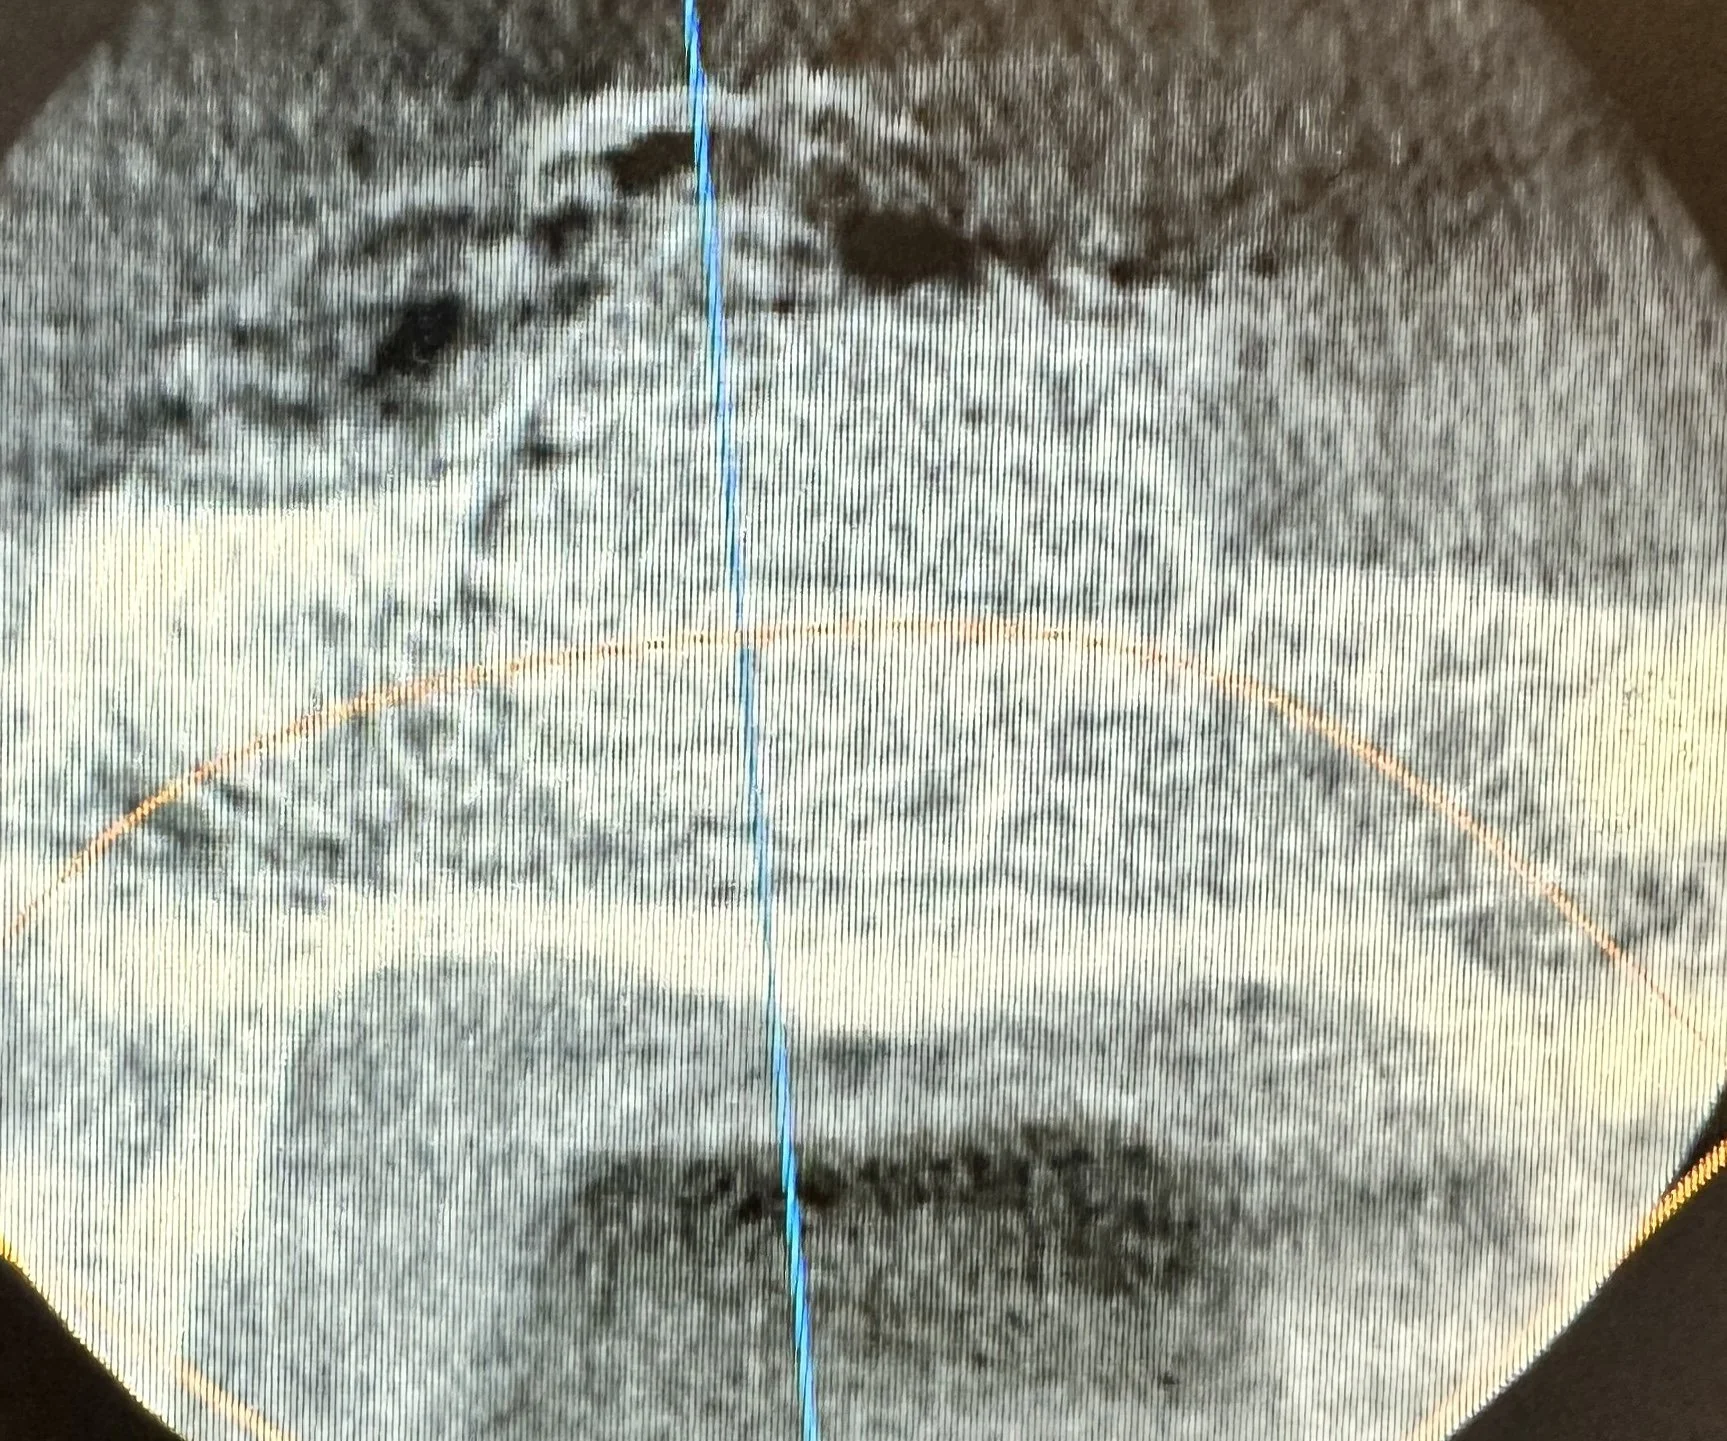

Post-operative CT imaging confirmed successful placement of the graft material in the previous area of bone destruction. The resorbable membrane served to prevent soft-tissue ingrowth and maintain graft stability during the healing phase, allowing bone turnover to occur gradually as the graft resorbed and new bone formed.

Guided bone regeneration plays a critical role in preserving structure and function following cyst removal. Proper membrane stabilization and graft selection support predictable bone regeneration — re-establishing a healthy foundation for future restorative options.